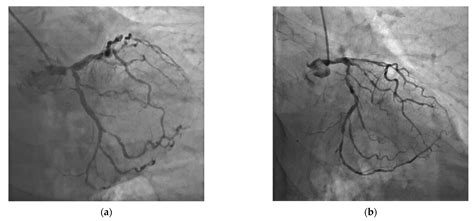

The Left Main Artery (often referred to in medical literature as the left main coronary artery or LMCA) is a relatively short vessel that emerges from the left aortic sinus. Despite its brevity, its responsibility is immense. It acts as the “trunk” of the left side of the heart’s vascular tree. Shortly after originating, it branches into two major pathways:

• Left Anterior Descending (LAD) Artery: This branch travels down the front of the heart and provides blood to the anterior wall and the septum, which separates the left and right ventricles. It is often referred to as the “widow-maker” due to the high mortality associated with its blockage.

• Left Circumflex (LCX) Artery: This branch wraps around to the left side of the heart, supplying blood to the lateral and posterior walls of the left ventricle.

Together, these branches ensure that the left ventricle—the heart’s primary pumping chamber—receives the high-pressure, oxygenated blood it needs to circulate life-sustaining fluids throughout the entire body.